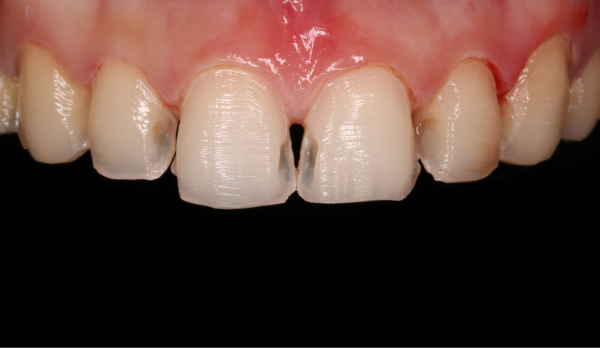

위 영상 자료는 미니쉬치과병원에서 미니쉬를 진행한 초상권 환자입니다

미니쉬 래미디 적용 사례

01.색상 모양 불만

01.색상 모양 불만